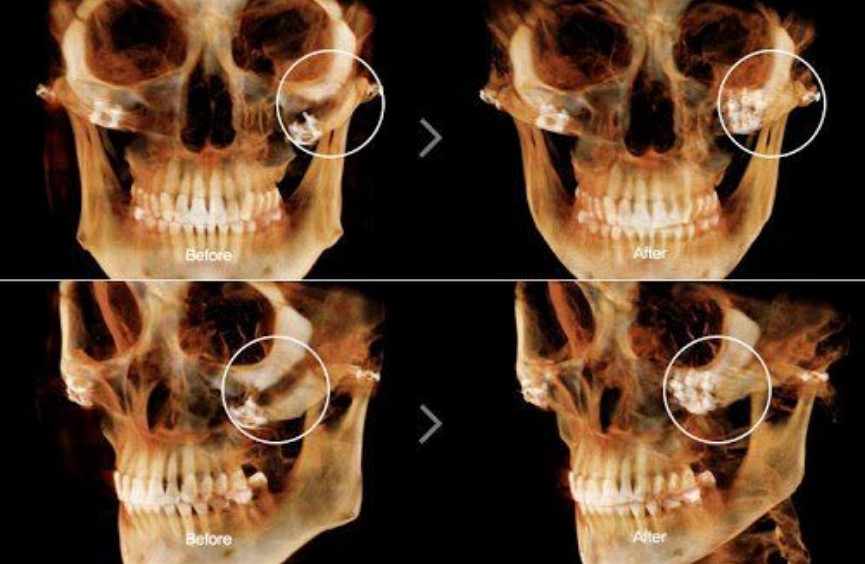

Vì vậy, khi phát hiện răng khôn mọc lệch hoặc đau kéo dài, người bệnh nên đến nha khoa để chụp CT Cone Beam 3D, giúp xác định chính xác vị trí và mối liên hệ thần kinh trước khi quyết định nhổ.

• Công nghệ hỗ trợ:

• Máy Piezotome (siêu âm) giúp cắt xương chính xác, giảm đau và sưng nề.

• Chụp CT Cone Beam 3D giúp quan sát rõ mối quan hệ giữa răng và dây thần kinh, giảm rủi ro tổn thương.